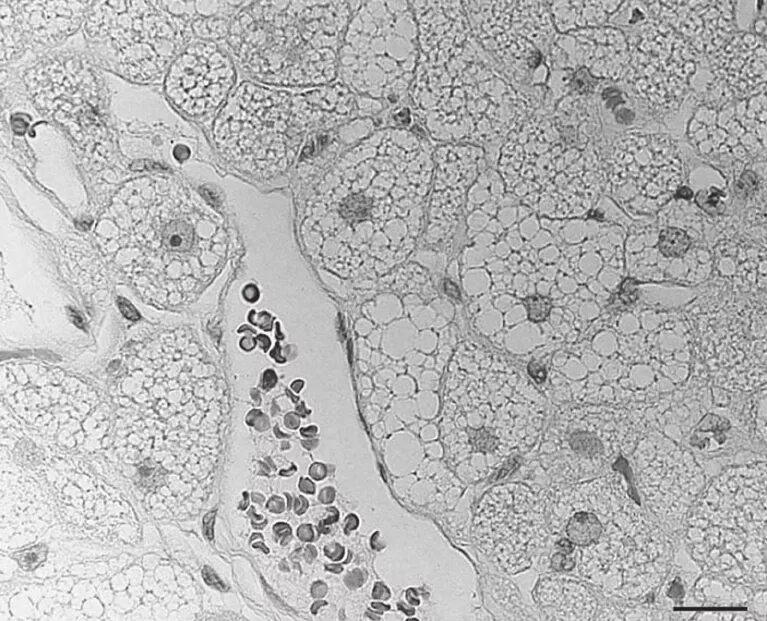

Броун рассматривал под микроскопом